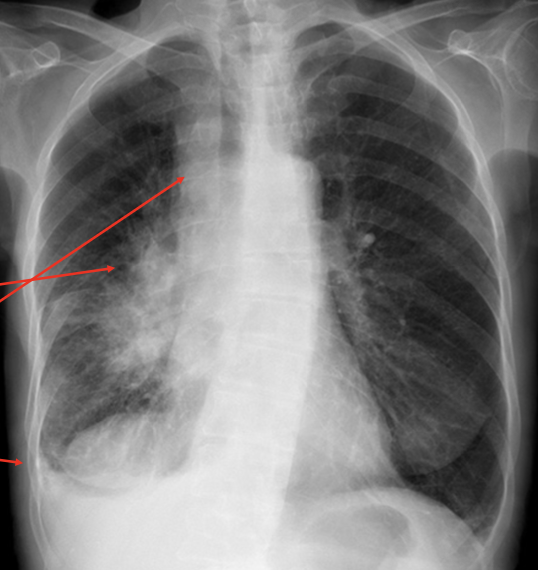

Pathology?

Pneumothorax